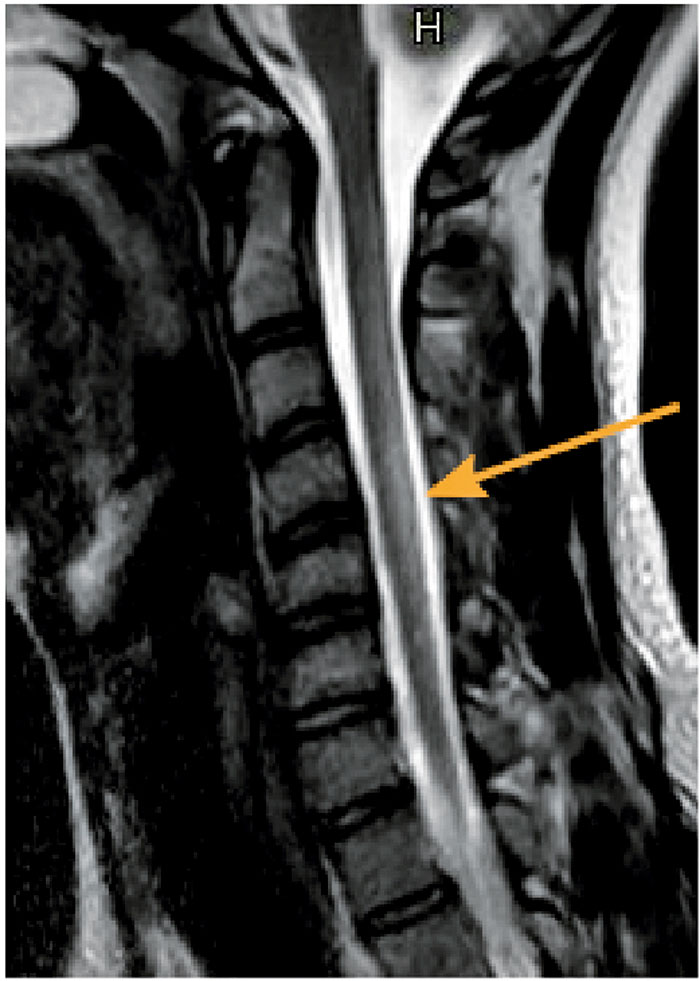

MR hjärna och helrygg visade en långsträckt cervikal högsignalförändring dorsalt bilateralt i medulla, från foramen magnum till C 6 (Figur 1), med misstänkt kontrastuppladdning från C 4 till C 6. Enstaka kontrastladdande nervrötter på T 12–L 1-nivå kunde inte uteslutas. Den radiologiska bilden var atypisk för Guillain–Barrés syndrom, varför ryggmärgsinflammation (mye­lit) misstänktes, möjligen neuromyelitis optica-spekt­rumsjukdom. Plasmaferesbehandling inleddes för att minska eventuell inflammatorisk aktivitet.

Figur 1. MR halsrygg vid inläggningen. Sagittal T2-viktad bild. Notera långsträckt dorsal högsignalförändring i halsryggmärgen (pil).